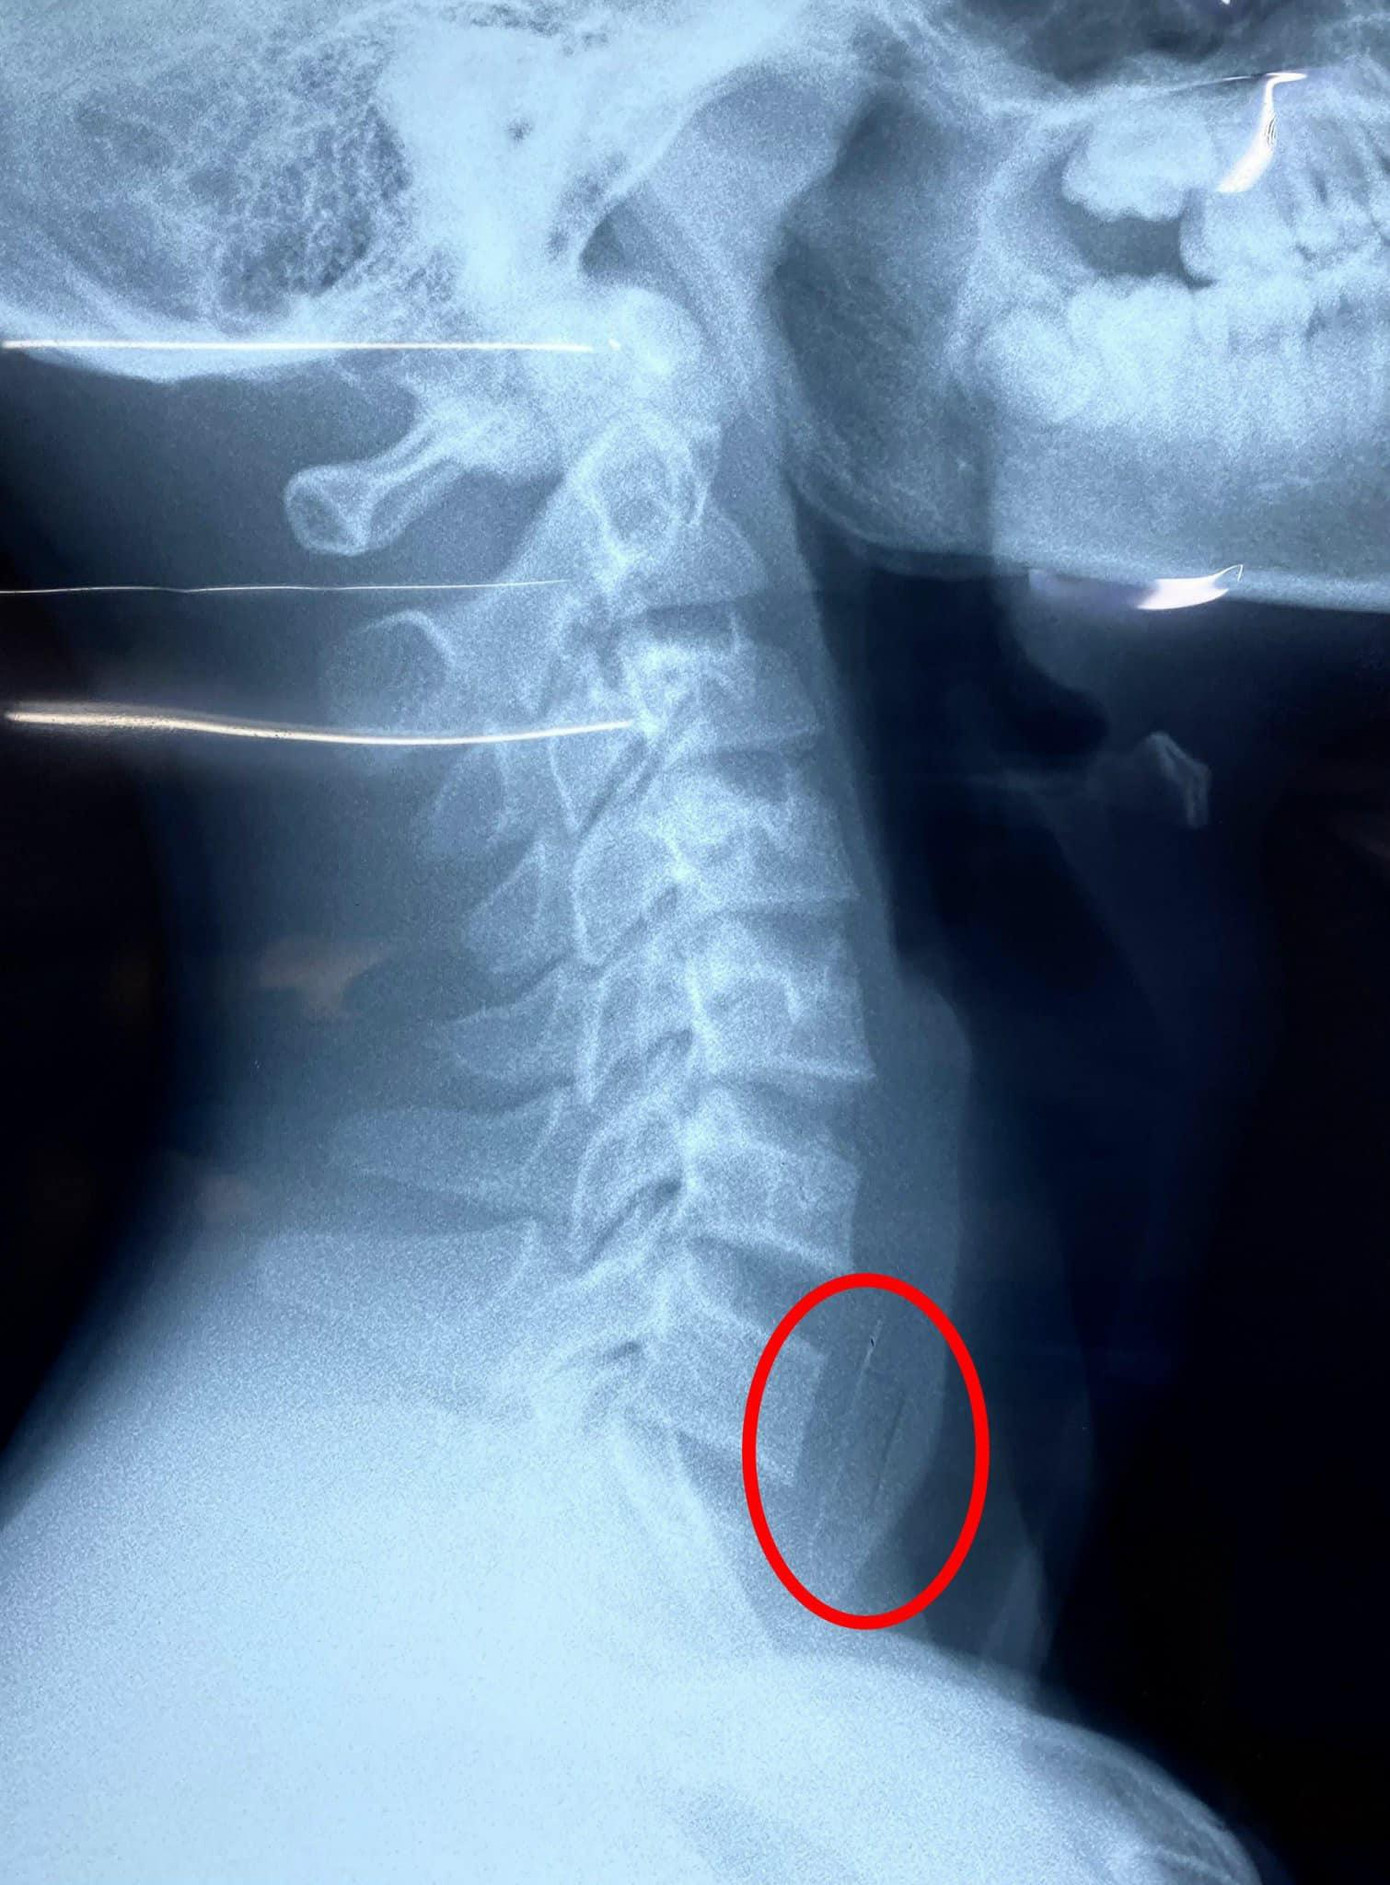

| Vị trí viên thuốc còn nguyên vỏ bị kẹt lại ở vùng thực quản của bệnh nhi |

Khai thác bệnh sử của bác sĩ từ phía gia đình ghi nhận, trước đó cậu bé bị sốt được người nhà mua thuốc về cho uống. Tuy nhiên, ngay sau khi uống, cậu bé ho nhiều, than đau họng. Các bác sĩ đã tiến hành chụp X-quang kiểm tra hình ảnh và ghi nhận dị vật cản quang ở vùng thực quản. Ngay lập tức bệnh nhi được chuyển đến khoa Tai Mũi Họng thực hiện nội soi cấp cứu.